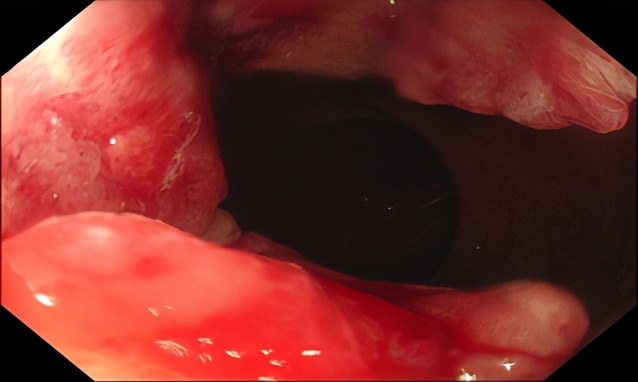

男,58岁,距肛1cm直肠腺癌,3b期,MRF+,复发风险极高危组,有强烈保肛愿望;接受同期放化疗,放疗结束6周后评价为临床完全缓解,接受观察等待疗法。观察至今(2020.11)无复发,肛门功能完全正常,生存质量良好。

图1a 治疗前肠镜(2016.8)